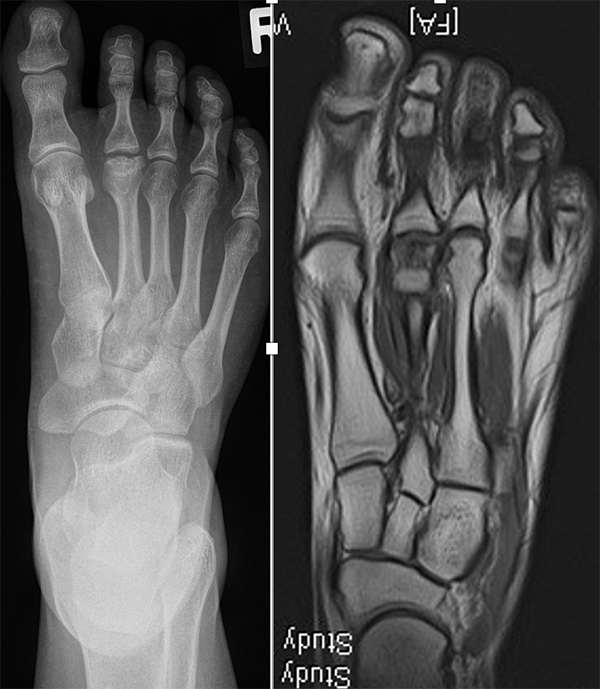

Diagnostisches Vorgehen

Damit die minimalinvasive Fußchirurgie zur Korrektur kindlicher oder jugendlicher Fußdeformitäten erfolgreich angewendet werden kann, erfordert die präoperative Diagnostik Röntgenbilder in drei Ebenen am stehenden Fuß. Röntgenbilder ohne Belastung des Fußes sind nicht zielführend. Im Fall von schweren Rückfußdeformitäten wird das obere Sprunggelenk in die radiologische Diagnostik mit einbezogen in Kombination mit der Rückfußaufnahme unter Belastung („Saltzman View“). Das OSG wird in zwei Ebenen geröntgt. Die streng seitliche Aufnahme des OSG kann bei den komplexen Fußdeformitäten mit der seitlichen Aufnahme des Fußes unter Belastung kombiniert werden. Das reduziert die diagnostische Strahlenbelastung der Kinder.

Indikationen für die beschriebenen Röntgenaufnahmen sind Klumpfußdeformitäten zur Beurteilung eines „flat top talus“ oder neurologische Grunderkrankungen mit varischer Fersenstellung wie zum Beispiel bei HSMN (Hereditäre Sensorische Motorische Neuropathie).

Sind Deformitäten komplexer Natur, sollte die CT mit einer 3D Rekonstruktion zur Anwendung kommen. Eine MRT-Diagnostik ist beim kindlichen Fuß zur Beurteilung von entzündlichen Prozessen, osteochondralen Läsionen, weichteiligen Traumafolgen oder im Fall von fibrösen Coalitiones von Bedeutung.